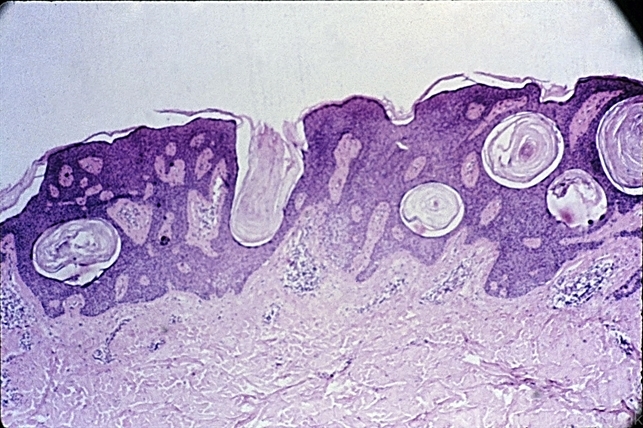

- basal cell, cyst, Keratosis pilaris (KP)

- Basal cell proliferation and keratin cysts of a typical seborrheic keratosis.